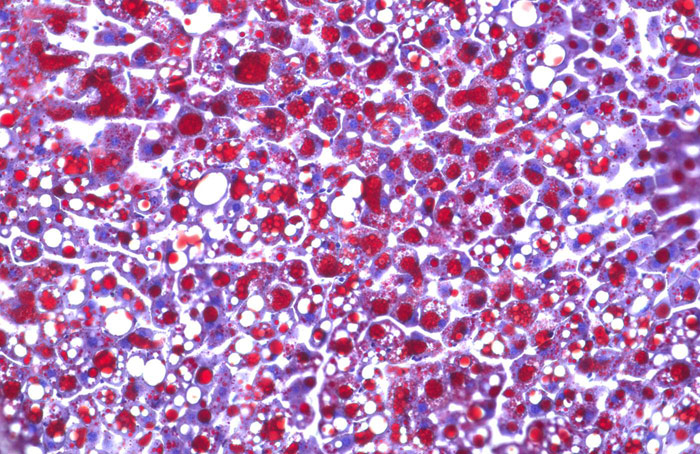

هذا في حين أصيبت فئران مجموعة المقارنة، التي عولجت بنفس الطريقة وبنفس العقار، بسكري الستيرويد. بل أنها صارت تعاني من البدانة ومن زيادة الدهون في الدم، كما اصيبت أكبادها بالتشحم.